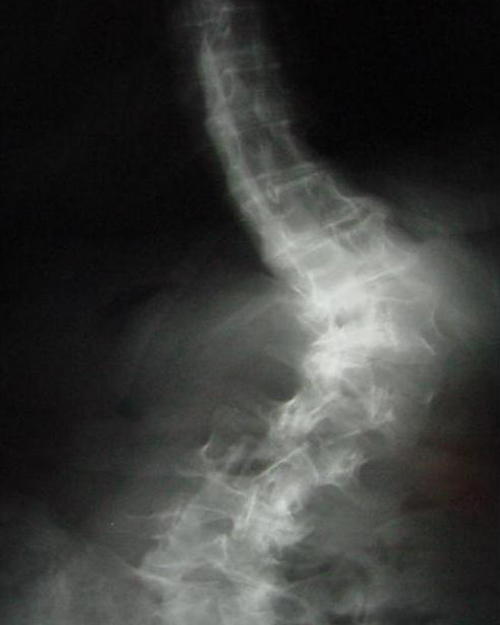

A free medical education seminar series for everyoneA FREE spine education seminar series for everyone Back pain has many faces and to many people it can be distressing, disabling or even frightening. Whether back pain comes from a strain, degenerative disc disease, a herniated disc, spinal stenosis, spondylolisthesis, a complex deformity or even a fracture, there are many options that can help you to live an active lifestyle. Additionally, osteoporosis is another disease that you may not even know you have. Learn from these dynamic experts about the various types of back problems and the latest treatments available. We will discuss the problems, the solutions and leave time for your questions to help you be active. Talk with the experts and get your concerns addressed. Spine Program